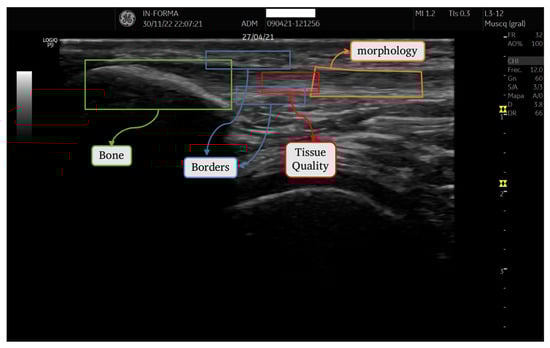

2.2.1. Regions of Interest (ROIs)

2.2.2. Quantifying Characteristics of ROI Images